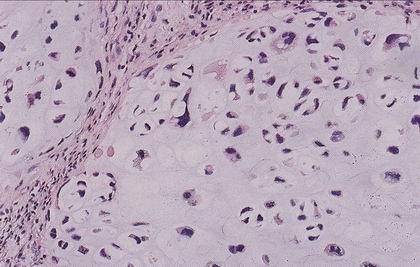

Spinocelulární karcinom

Verrucous carcinoma

Varianta spinoca s velmi dobrou prognózou

Definován

verukózním růstem

minimálním stupněm cytologické atypie

ostře ohraničeným růstem proti spodině (byť může infiltrovat hluboko)

Diagnózu VC z probatorní excize není možno podle uvedené definice stanovit, lze jen vyslovit suspekci.